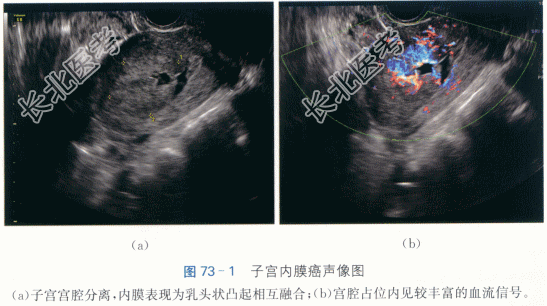

子宫内膜样腺癌(Ⅱ级、ⅢC1期)。